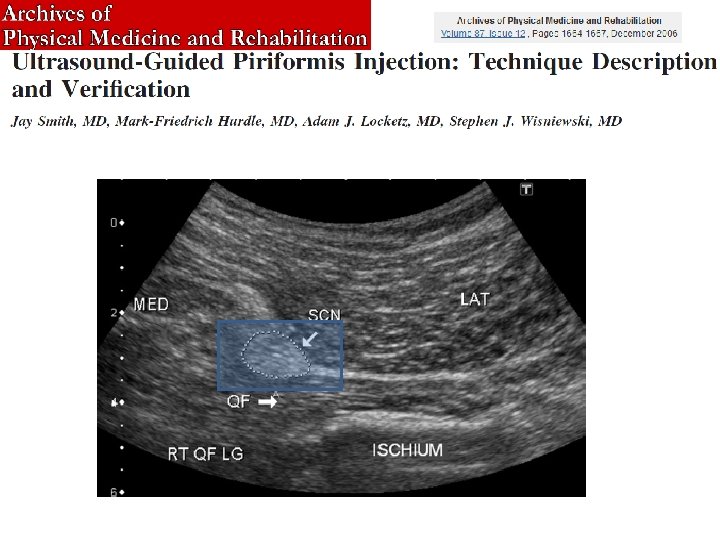

Confronto di accuratezza tra infiltrazioni del piriforme con guida fluoroscopica vs guida ecografica Risultati: • Guida fluoroscopica bersaglio raggiunto 6/20 • Guida ecografica bersaglio raggiunto 19/20